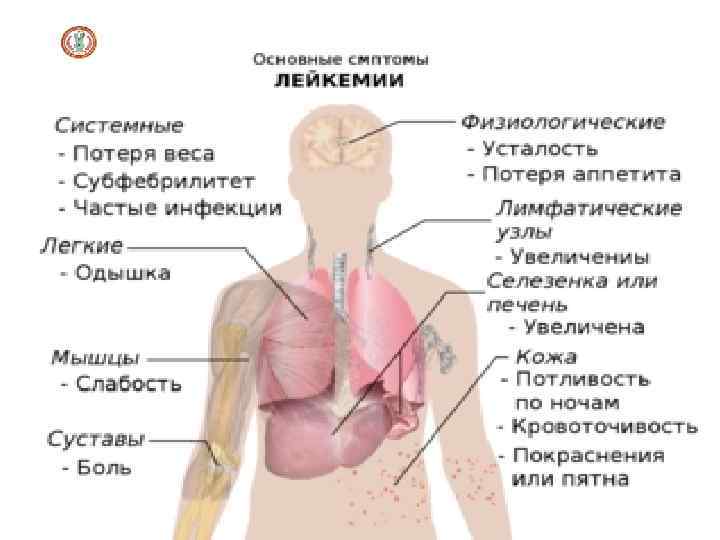

Клиническая картина острых лейкозов

Клиническая картина острых лейкозов (синдромы) • Анемический синдром: бледность, одышка, сердцебиение, сонливость. • Инфекционно-некротический синдром (склонность к инфекциям бактериальным, грибковым и вирусным). • Геморрагический синдром. При осмотре выявляют петехии и экхимозы на коже (самопроизвольные, в местах инъекций, механического трения). Возможны интенсивные носовые и тяжёлые внутренние кровотечения (метроррагии, желудочно-кишечные кровотечения, кровоизлияния в мозг). • Гиперпластический синдром (лимфаденопатия): лимфатические узлы множественные, плотные, эластичные, округлые, могут быть спаяны друг с другом, разных размеров (от 1 до 8 см); их пальпация безболезненна, увеличение брыжеечных лимфатических узлов, гипертрофия червеобразного отростка, гипертрофия внутригрудных лимфатических узлов. Печень и селезёнка увеличены. Гипертрофия дёсен, лейкемиды кожи (специфические узелки). В средостение наблюдается гипертрофия тимуса, что может вызвать сдавление органов средостения)

Клиническая картина острых лейкозов Признаки специфического поражения: • Интоксикация: лихорадка, снижение массы тела, снижение аппетита, слабость, усиленная потливость. • Болезненность костей (особенно трубчатых, позвоночника), артралгии. • ДВС-синдром. • Нейролейкемия. (поражение центральной нервной системы) возникает особенно часто при остром лимфобластном лейкозе и значительно ухудшает прогноз. Возникновение нейролейкемии обусловлено метастазированием лейкозных клеток в оболочки головного и спинного мозга или в вещество мозга (интратумор, прогностически более тяжёлый тип опухолевого роста). В неврологическом статусе возможны проявления различной тяжести - от лёгкой общемозговой симптоматики (головная боль) до очаговых поражений (нарушение сознания, нарушение зрения, дискоординация движений, дисфазия)